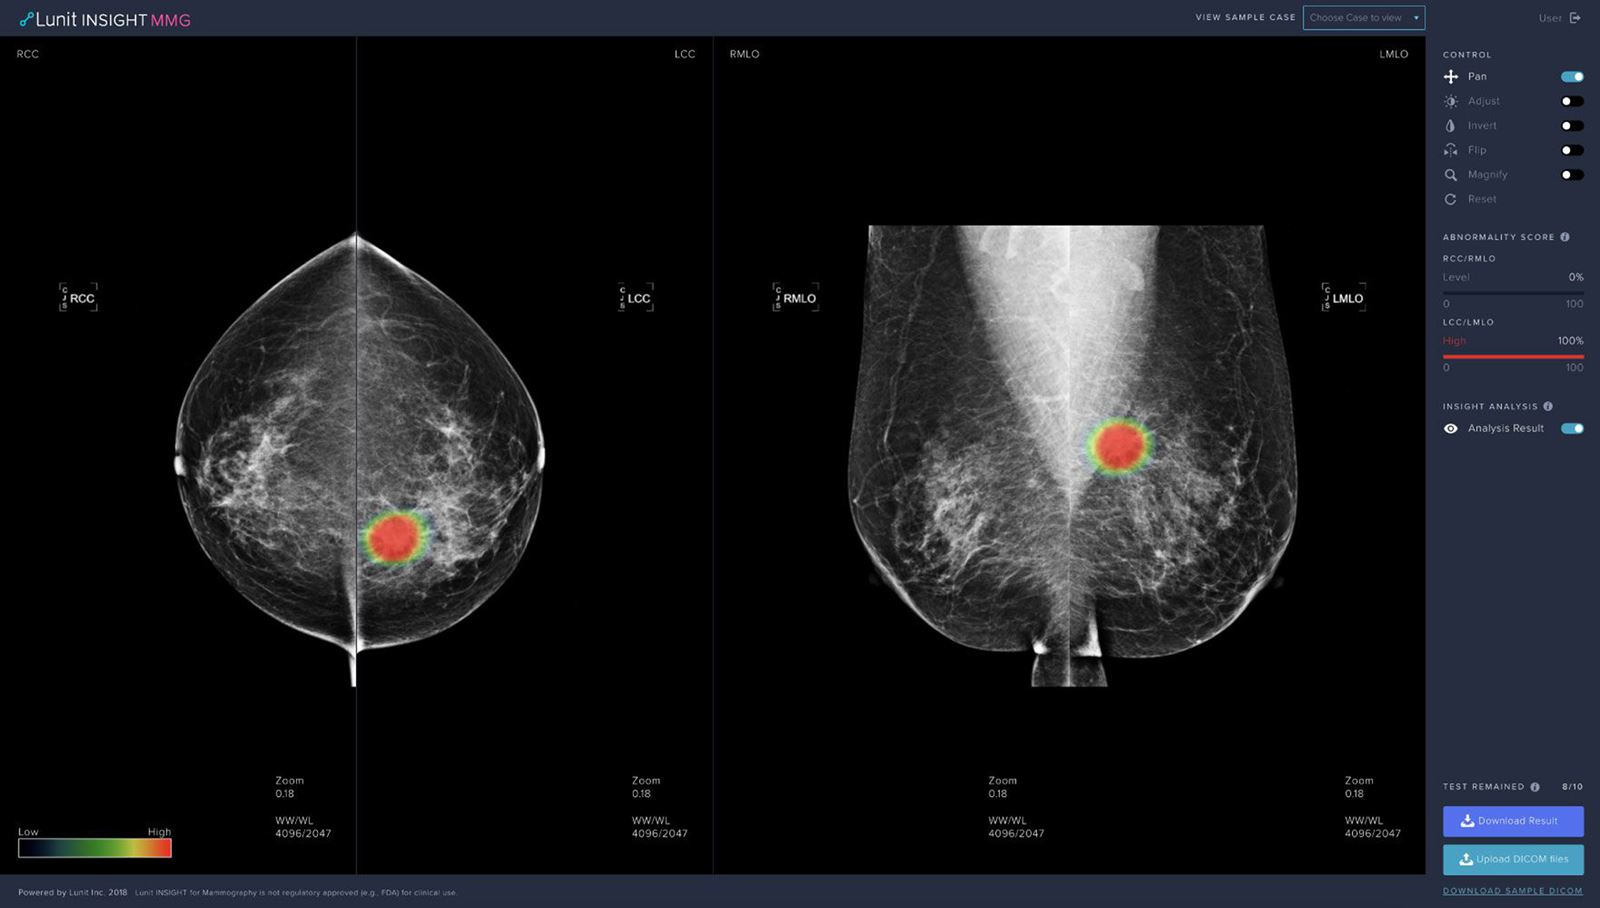

직관적으로 말하자면 효과적인 진단과 치료에 도움을 주는 서비스와 제품 개발이 루닛이 하고 있는 일입니다. 영상진단에 도움을 주는 루닛 인사이트(Lunit INSIGHT) 제품군과 항암제에 대한 치료 반응을 예측해 주는 루닛 스코프(Lunit SCOPE) 제품군입니다.

첫 번째, 효과적인 진단을 위해서 흉부 엑스레이(Lunit INSIGHT CXR)와 유방촬영술(Lunit INSIGHT MMG) 분석에 대한 인공지능 기술을 특화시켜 제품화 했습니다. 그 이유는 위의 2가지 방법이 암을 검진하는 데 가장 널리 쓰이는 진단이고, 다수의 환자에게 도움이 될 수 있다는 판단 때문이었습니다. 이에 대한 결실로 작년에 식약처 허가와 유럽 CE 인증을 받았습니다.

덕분에 현재 루닛의 진단 제품들은 국내 주요 종합병원은 물론, 1~3차 병원과 보건소 등에서 사용 중입니다. 해외에서는 멕시코, 아랍에미리트연합, 중국, 태국, 대만 등에서 흉부 엑스레이 및 유방촬영술 영상 분석에 사용되고 있습니다.